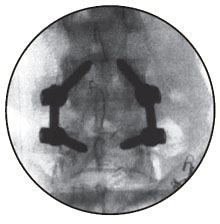

The nerve roots are then moved to one side and the disc material removed from within the centre of the disc.A cage is then inserted into the disc space. The cage preserves the height of the disc space and acts as a bridge, or scaffold, through which new bone can grow. Screws and rods are inserted to stabilize the spine while the treated area heals and fusion occurs, as the ultimate goal of the procedure is to restore spinal stability.